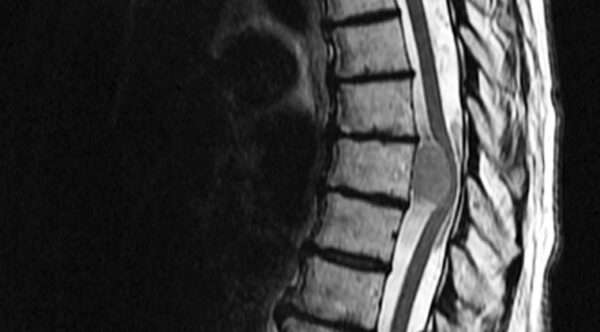

La imagenología juega un papel crucial en el diagnóstico de los tumores espinales, ya que permite identificar y localizar la lesión con alta precisión. La resonancia magnética con contraste (RM) es la herramienta de elección debido a su capacidad para proporcionar imágenes detalladas de los tejidos blandos, permitiendo una visualización clara de la médula espinal, las raíces nerviosas y las estructuras circundantes. El uso de contraste mejora aún más la capacidad de la RM para detectar lesiones tumorales, ya que las áreas de crecimiento tumoral suelen captar el contraste de manera diferente a los tejidos circundantes, lo que facilita su identificación.

Por otro lado, la mielografía por tomografía computarizada es otra técnica valiosa, especialmente en casos en los que la RM no está disponible o no es concluyente. La mielografía consiste en la inyección de un medio de contraste en el espacio subaracnoideo, lo que permite visualizar la médula espinal y las raíces nerviosas a través de la tomografía computarizada. Esta técnica es particularmente útil para evaluar la compresión de la médula espinal o las raíces nerviosas provocada por tumores espinales, ya que el medio de contraste resalta las estructuras anatómicas y las posibles alteraciones causadas por la presencia de la masa tumoral.

La indicación de realizar una de estas pruebas de imagen con urgencia se basa en la combinación de varios factores. En primer lugar, si un paciente presenta antecedentes de un tumor en otra parte del cuerpo, como en el caso de las metástasis, y además experimenta dolor en la espalda, esto aumenta la sospecha de que la causa sea un tumor espinal. A este dolor en la espalda se le pueden asociar hallazgos anormales en las radiografías simples de la columna vertebral, como alteraciones en la alineación ósea o signos de compresión vertebral. Adicionalmente, los síntomas neurológicos que sugieren compresión de la médula espinal, como debilidad, alteraciones sensoriales o pérdida de control motor, deben llevar a la realización urgente de estudios de imagen para identificar y localizar con precisión el tumor y evaluar la extensión de la lesión.